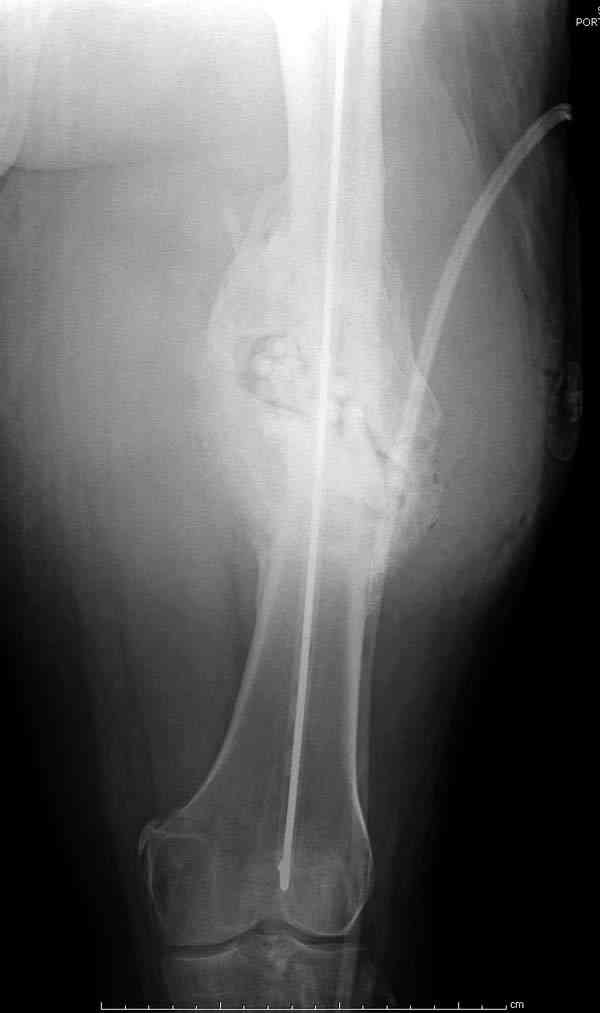

На ренгенограмме явный остеомиелит с секвестром, секвестерэктомия из медиального доступа и замена старого антибиотического гвоздя на новый.

После трех дней ваккуумного дренажа, из латерального доступа удаление остатков старых антибиотичеких бус, закрытие медиальной раны с наложением ваккуумирования латерально. В следующий раз, через пару дней надеемся закрыть рану.

удаление

подготовка гвоздя

7-8 послеоперационные